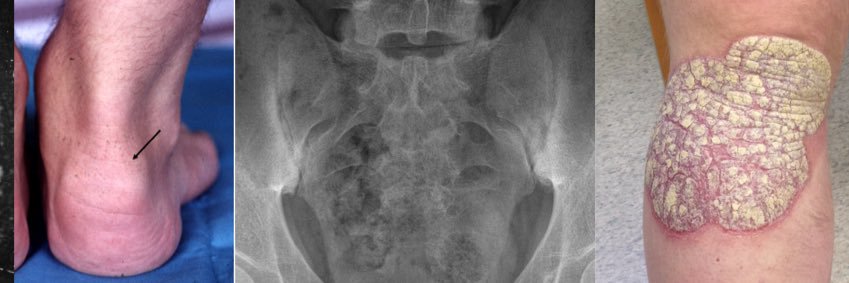

🚨As we near the 60th anniversary of #PsoriaticArthritis being “officially” recognized as a distinct disease, @LeedsTeamSpA & I take great pleasure in sharing this collection of papers that provides a holistic update on PsA. #PsoriasisAwarenessMonth clinicaltherapeutics.com/article/S0149-…